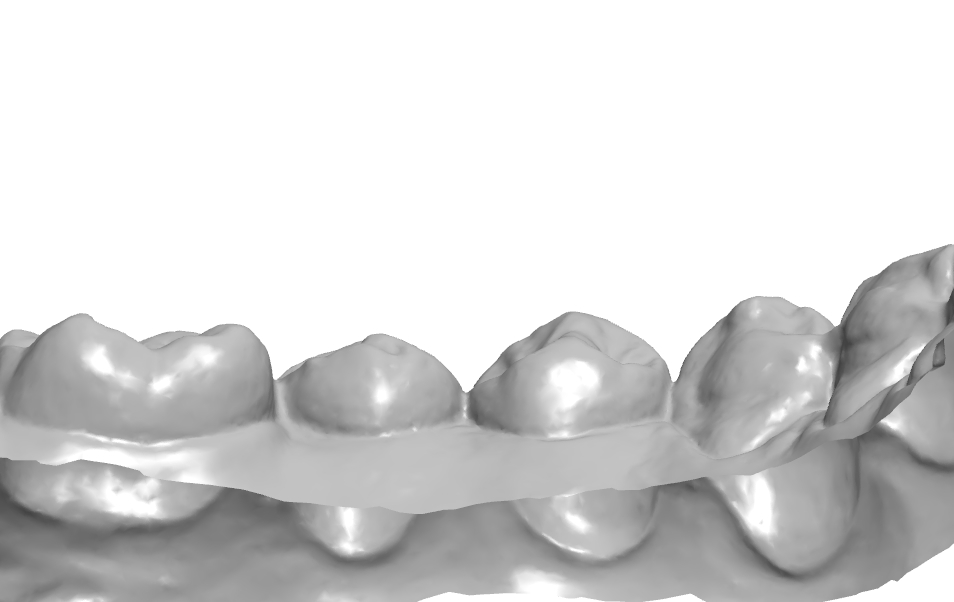

1치대2치 관계

치아의 수평피개 체크

각 치아의 풍융도 체크.